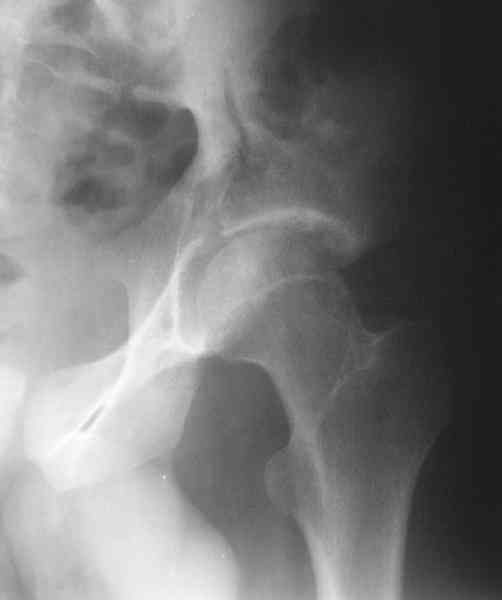

Мужчина 33 лет получил травму в шахте (придавило вагонеткой) 6 недель назад. Изолированное повреждение вертлужной впадины.

В местной больнице отлежал несколько недель на вытяжении. После выписки амбулатрный травматолог направил в институт. На сегодня, похоже, уже имеется неправиильное сращение. См. картинки.

Dear all,A male 23 y.o. injured 6 weeks ago - mine trauma, impacted by a carriage. Isolated injury of the acetabulum. At the initial hosptial was on bed traction some weeks. After discharge visited anotheк orthopaedic surgeon who referred him to our unit. To date looks like a malunion. Images attached. The question is about what to do now - either leave it as is or perform open reduction? If the latter what approach, reduction manoeuvres and fixation would you advice? Thx in advance!

What is your indication for surgical management? What kind of fracture do you think it is? It looks like a transverse type although it has been a couple of years since I looked at an acetabular fracture.

My concern would be that the risk of leaving it malreduced is very high. It appears to be primarily a gap rather than a step in the articular surface. Do you have any CT views that show an articular step?

The last two images from the 3-D CT scan certainly makes the fracture look worse than the plan radiographs.

The anterior element of the fracture is so low and the anterior roof arc angle must be at least 60 deg.

The posterior element is so minmally undisplaced. There is good congruence of the joint, and to top it all, 6 weeks have passed. If you consider ORIF now, I don't expect that much improvement could be accomplished. Not to mention the need for extensive approaches with their morbidity.